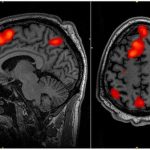

By exposing mice to a unique combination of light and sound, MIT neuroscientists have shown that they can improve cognitive and memory impairments...